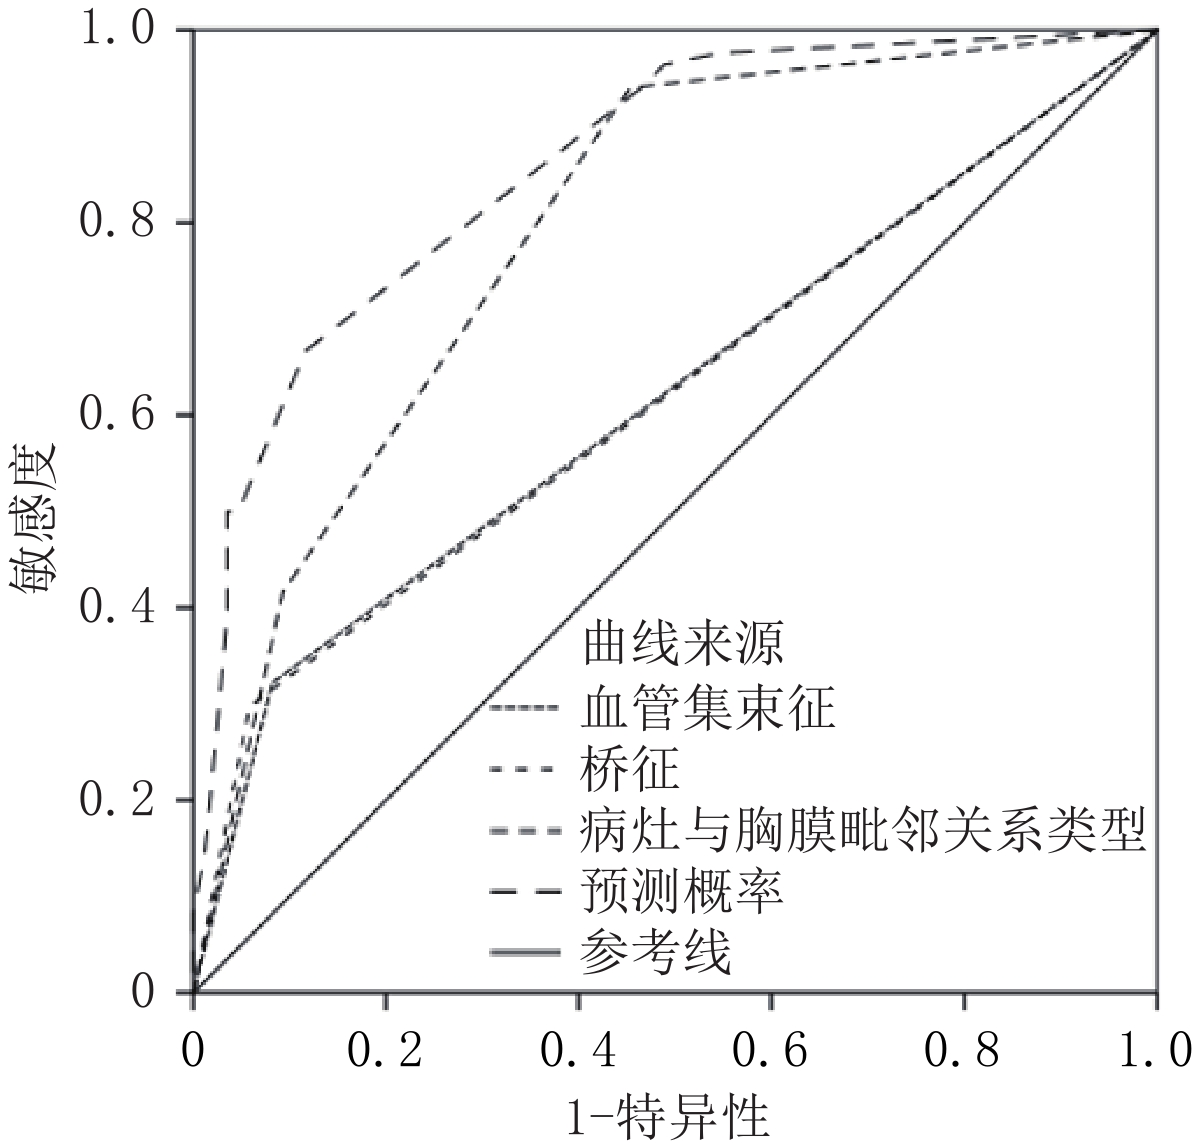

利用桥征、血管集束征、病灶与胸膜毗邻关系、Logistic模型预测概率对早期胸膜下肺腺癌脏层胸膜侵犯情况预测,最佳截断值分别为0.50、0.50、0.50、56.25%,约登指数分别为24.00%、23.95%、48.70% 和55.04%。Logistic模型预测概率对早期胸膜下肺腺癌脏层胸膜侵犯情况预测的效能最佳(表3、图1和图2)。

表 3 早期胸膜下肺腺癌脏层胸膜侵犯CT影像学特征预测价值Table 3. Predictive value of CT imaging features of visceral pleural invasion in early subpleural lung adenocarcinoma项目 最佳截断值 ROC曲线下面积 诊断灵敏度/% 诊断特异度/% 约登指数/% 血管集束征 0.50 0.620 32.14 91.86 24.00 桥征 0.50 0.620 29.76 94.19 23.95 病灶与胸膜毗邻关系类型 0.50 0.794 94.05 54.65 48.70 Logistic模型预测概率 56.25% 0.861 66.67 88.37 55.04 表 4 ROC曲线下的成对样本区域差异Table 4. Regional differences in paired samples under the ROC curve检验结果对 统计检验 Z P 血管集束征-桥征 0.007 0.995 血管集束征-病灶与胸膜毗邻关系类型 -4.189 0.000 血管集束征-Logistic模型预测概率 -7.194 0.000 桥征-病灶与胸膜毗邻关系类型 -4.155 0.000 桥征-Logistic模型预测概率 -7.694 0.000 病灶与胸膜毗邻关系类型-Logistic模型预测概率 -3.649 0.000 3. 讨论